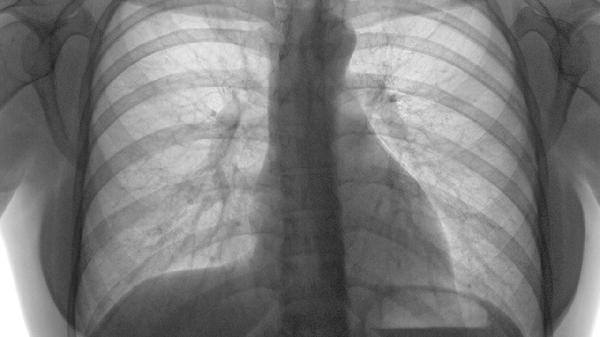

肋软骨炎是肋软骨常见病变,表现为局部疼痛肿胀,可能与外伤、劳损或感染有关。肋骨骨折多由直接暴力导致,可出现剧烈疼痛、呼吸困难等症状。肋软骨钙化属于退行性改变,影像学检查可见高密度影。肋骨肿瘤较为罕见,需通过病理检查确诊。胸廓畸形如鸡胸、漏斗胸等疾病与肋软骨发育异常相关。